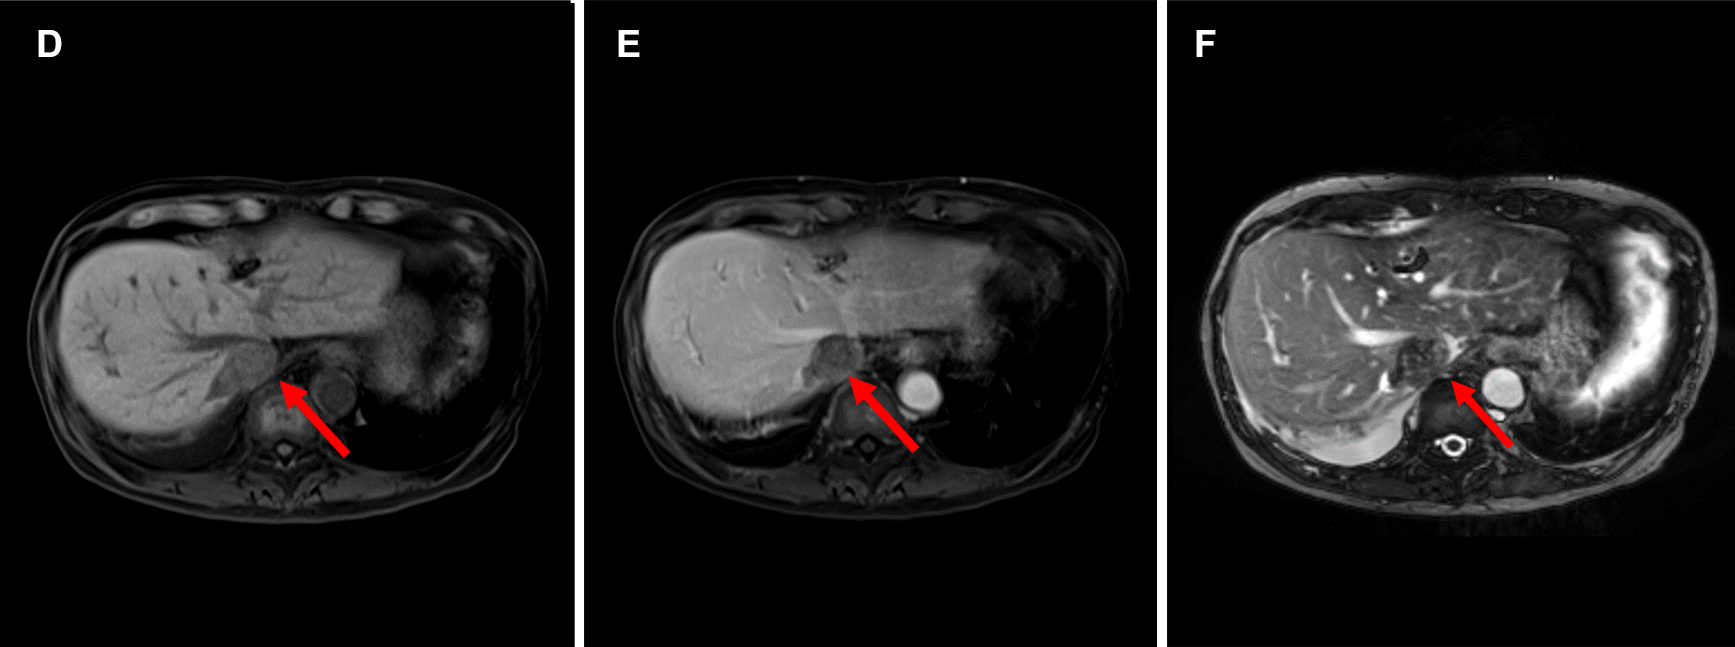

図2.ガドビスト造影MRI (A:T2WI B:DWI(b=800) C:ADCmap D:造影前脂肪抑制T1WI E:造影後脂肪抑制T1WI F:造影後True FISP G:造影後TrueFISP冠状断像)

(A-F→)下大静脈内の腫瘍はT2WI低信号で、DWIで不均一な高信号、ADCは軽度低下している。hypovascularであり、造影True FISP冠状断像で頭側は右房内(➤)、尾側は右腎静脈起始部(⇒)、左腎静脈(➔)に及んでいることがわかる。

転移性肝腫瘍の経過観察でプリモビストMRIを行っており、心臓超音波後、hypovascularな下大静脈内腫瘍がプリモビストMRIでも確認された。腫瘍進展範囲の精査としてガドビストMRIを施行。Slow infusion造影(6倍希釈した造影剤を6分間流し続ける)のTrue FISPを加え、腫瘍周囲の血管を乱流の影響を抑え、常に高信号に描出することでhypovascularな腫瘍の正確な進展範囲が評価可能であった。